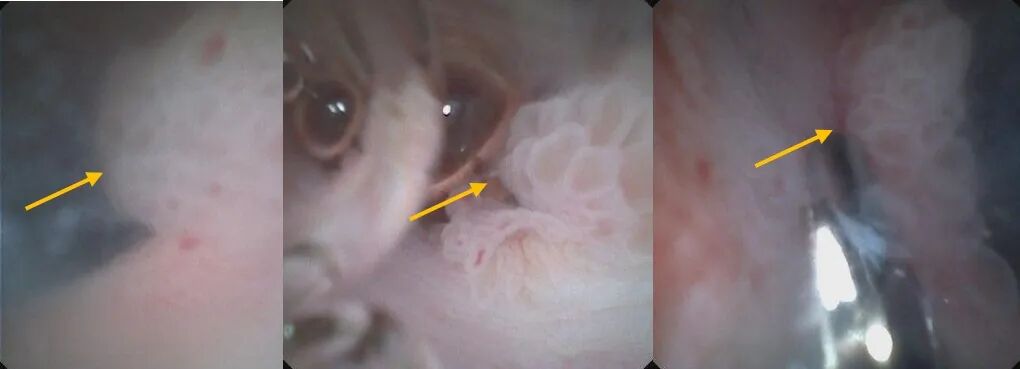

同期,另一位八十多岁的大娘因间断腹痛入院。完善影像检查后提示“胆总管结石可能性大”,为了进一步治疗,内镜科团队为其进行ERCP(逆行性胰胆管造影)。

可奇怪的是,ERCP术中注入造影剂后却未见结石踪影,一台看似普通的ERCP取石手术却陡然变得扑朔迷离!结石究竟隐藏在何处?

640?wx_fmt=jpeg&from=appmsg

ERCP造影未见结石,箭头所示为胆道(左图),ERCP术中胆道球囊阻塞造影亦未见结石,箭头所示为球囊(右图)

时间在一分一秒地过去,是结石已经自己排掉?还是结石躲藏在更深处常规ERCP无法发现?考虑病人高龄,身体条件差,一旦漏掉结石再次发病后果不堪设想,团队马上启用备用方案,应用胆道子镜探寻结石!胆道子镜进入胆管内,首先于胆囊管搜寻,未见结石。然后进入肝内胆管一级分支亦未发现结石,紧接着子镜进入狭小的二级胆管逐一排查,终于发现,结石已偷偷地从胆总管“逃”到了肝内胆管!紧接着一个难题是如何把结石取出,传统的ERCP手术对位于肝内胆管的结石几乎束手无策,普通ERCP手术器械在如此狭小的空间无法施展。经过讨论,团队改变治疗策略,决定用子镜下微细网篮尝试取石,通过在狭小的空间内仔细观察、谨慎处理、反复调整,历时半个多小时的精细操作,终于将结石拖入胆总管,随后成功取出了结石!